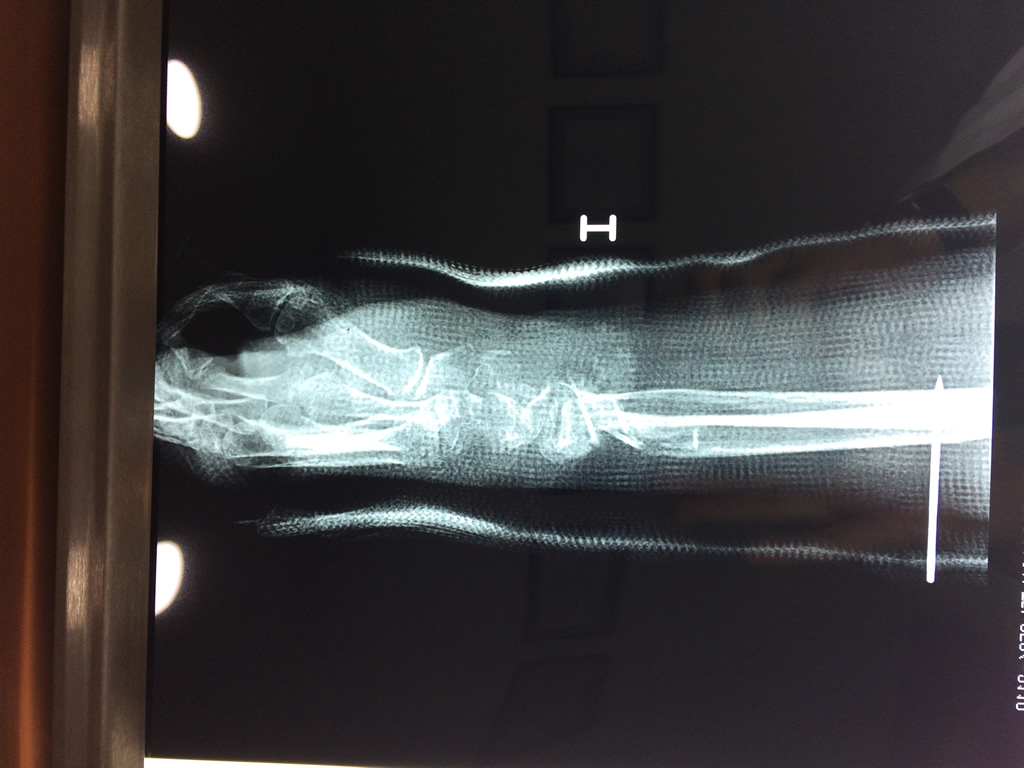

Cirugía de Muñeca y Mano

Los procedimientos más comunes en cirugía de la mano son aquellos destinados a reparar traumatismos, incluyendo lesiones de tendones, nervios, vasos sanguíneos, y articulaciones; huesos fracturados; y quemaduras, cortes, y otros daños de la piel.